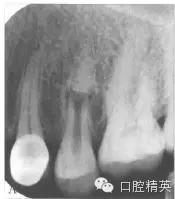

X線片示:上頜第二前磨牙根中部折斷,斷端呈喇叭口狀。斷端根尖段根管影像消失,牙周膜間隙未見明顯異常,斷端根中上段根管粗大,斷端周圍弧形低密度影像(圖2)。牙膠示蹤片示瘺管來源于斷端。

圖2 初診X線片。